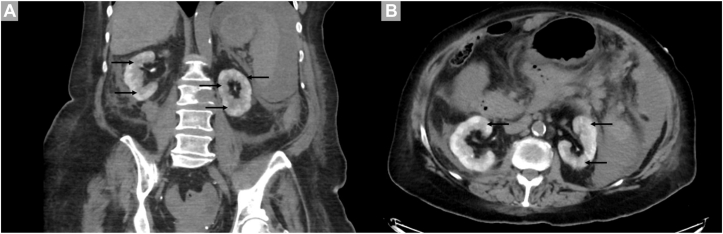

Clinical Implications of Striated Nephrogram in Patients Receiving Immune Checkpoint Inhibitors for Cancer.